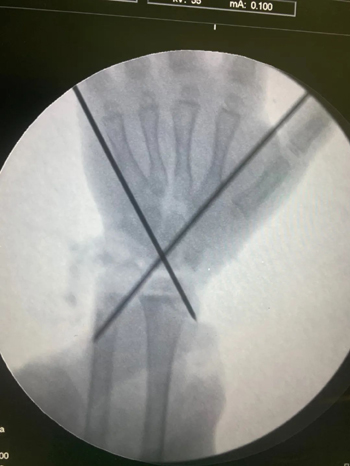

断肢再植成功!术中x线及肢体再植成功后通血变红。